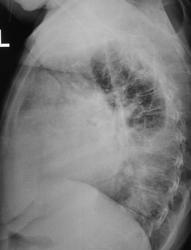

С подозрением на пневмонию направлен на рентгенографию ОГК

Объемное давление в плевральной полости слева (выпот, видна косая граница в прямой проекции), оттесняющее средостение вправо(трахея наглядна). ЛГБ вроде проходим, дальше - тьма. Затенение переднего легочного пространства в боковой проекции, радиарная тяжистость инфильтрата слева, увеличение правого корня, кругляш в S9 слева на боковой - накопано богато. Вероятны дела онкологические, средостенные в легкое иль наоборот (что менее вероятно), однако мтс плеврит и в паренхиму наиболее реальны.

Я сначала тоже про жидкость подумала, но где она на боковом? Осумкованный выпот не смог бы так подвинуть средостение. Я думаю, в левом легком очень большая опухоль

Предполагал как и Вы. Но, если большая опухоль в левом легком, то где она на боковом снимке? Не напрашивается ли патология в средостении?

На боковом - в передних отделах легкого в проекции сердца. Патология в средостении тоже может быть, почему нет.

А если это все-таки плеврит, где же он на боковом?? ЗЫ. Теперь вижу, смутила малая интенсивность жидкости на боковом снимке

Признаки  центрального новообразования левого легкого, с ателектазом верхней доли, компенсаторное вздутие нижней. Динамика= уменьшению перипроцесса.